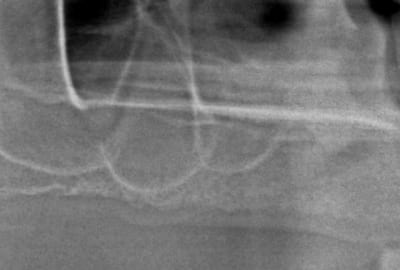

premiers implants posées avec Pilot.

patient sous plavix impossible de suspendre le traitement

implant dans septum sinisien bridge posé en 2008

à main levé ; bonne chance

(c'était la première interface machine)

Screenshot873 w7ixfi - Eugenol

Img 0807 i1bcnt - Eugenol

Bontemp 2 ale85h - Eugenol

Img 0801 amerxh - Eugenol

Pano pre op msig1i - Eugenol

16 2y p1ygeq - Eugenol

quand je regarde attentivement tes deux coupes elle sont visiblement pas au même niveau sur le prévisionnel l'implant est dans le trou palatin postérieur alors que l'implant est placé plus antérieur surement 3 ou 4 mm,les implants ne semblent pas être de la même longueur non plus, je ne comprend pas le sens de la démonstration ; si ce n'est que tu es un grand un chanceux tu devrais jouer au loto

jumpingjackflash écrivait:

--------------------------

> quand je regarde attentivement tes deux coupes elle sont visiblement pas au même niveau sur le prévisionnel l'implant est dans le trou palatin postérieur alors que l'implant est placé plus antérieur surement 3 ou 4 mm,les implants ne semblent pas être de la même longueur non plus, je ne comprend pas le sens de la démonstration ; si ce n'est que tu es un grand un chanceux tu devrais jouer au loto

Exemple type des posts sur internet...je lis ce que j'ai envie de comprendre... si tu regarde attentivement, et que tu lis le texte, 1 implant est posé, en 26 et en 16 il va être posé (c'est fait depuis), donc il est normal que les coupes ne soit pas au mème niveaux ...

Je ne suis ni un chanceux,ni spécialement doué, simplement avant la chir je m’imprègne de la vue 3D et je vais là ou mes sensations me guident, exactement comme en endo...